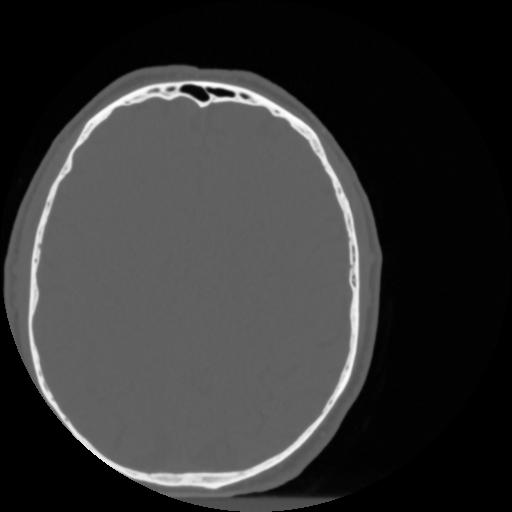

4 CEREBRO,,Vol,0.5,CEREBRO,,